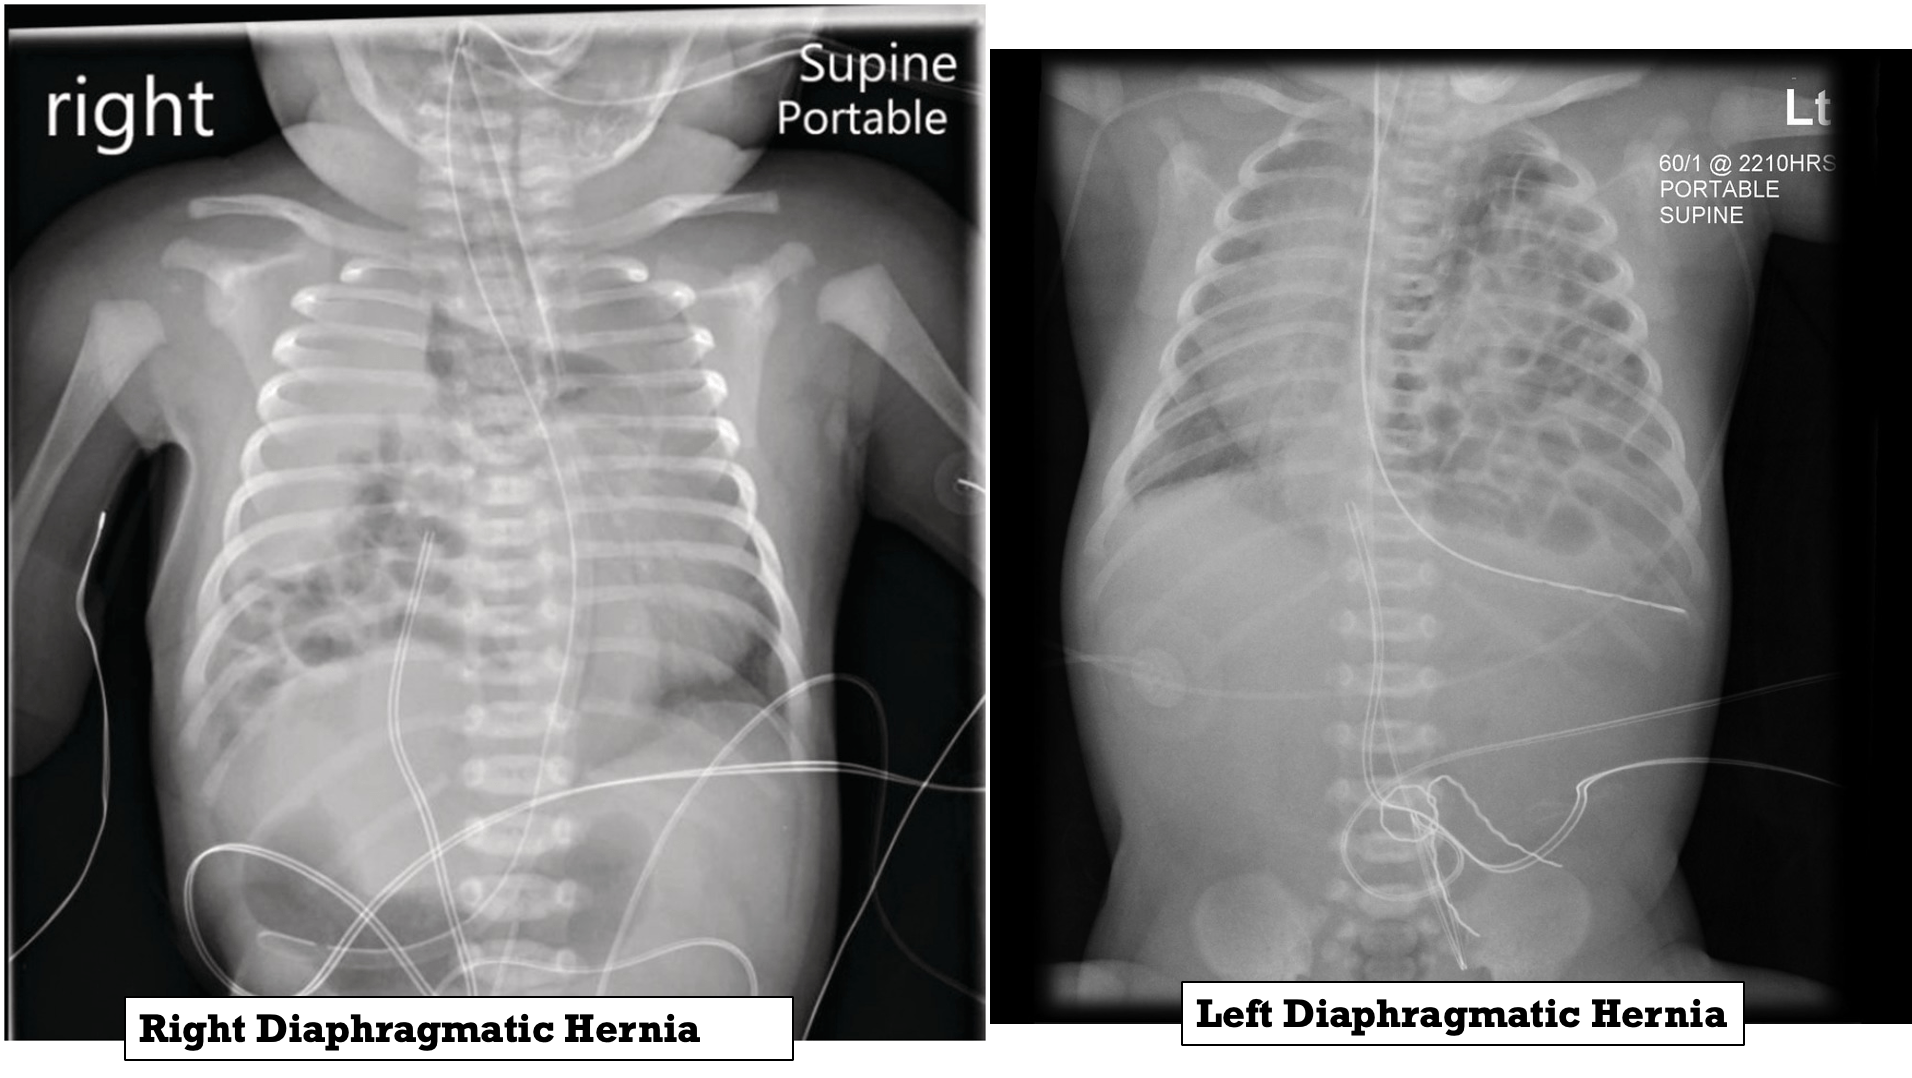

Occurs when the diaphragm fails to completely close during development, allowing for abdominal contents to enter the chest cavity. 85% occur on the left side and 15% occur on the right side.

- Chest radiography: to confirm diagnosis of congenital diaphragmatic hernia

A newborn with left congenital diaphragmatic hernia.

Note the scaphoid abdomen and the barrel-shaped chest.

The diagnosis is made or confirmed by radiograph.